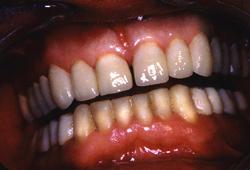

Vue finale

Avant.

Après avec augmentation de la DVO de 6 mm.

Les 14 couronnes supérieures céramo-céramiques sont collées.

Les 14 Couronnes céramo-céramiques mandibulaires collées.